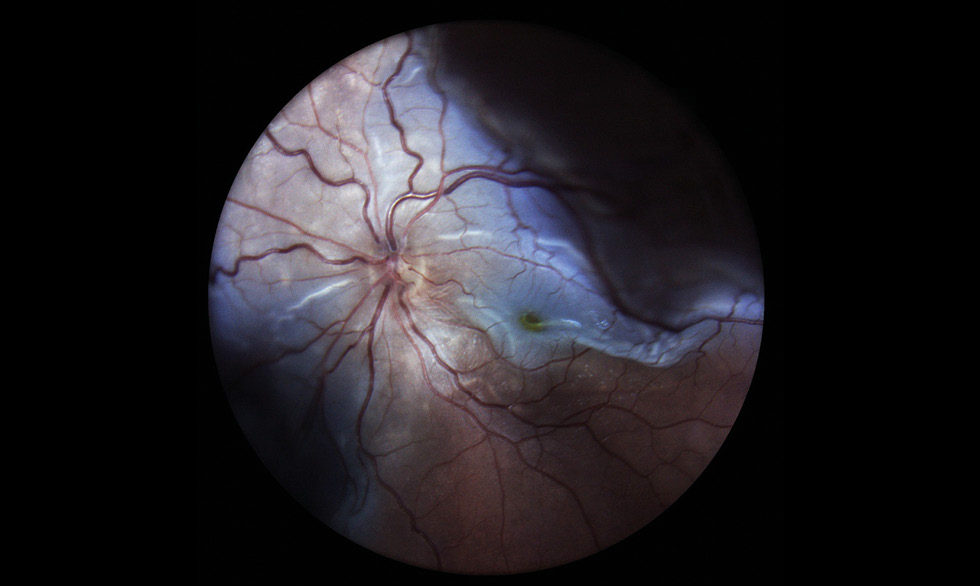

RESULTS: This article presents the clinical case of postoperative choroidal detachment in a child with Sturge–Weber–Crabbe syndrome after microinvasive non-penetrating glaucoma surgery. Against the background of the existing anomalies in the development of an optic disc after antiglaucomatous intervention for decompensated glaucoma, after the normalization of IOP, the patient developed choroid detachment with exudative retinal detachment the next day of operation. After conservative therapy involving bed rest and double instillation of mydriatics for 1 month, the situation was completely resolved and his vision was restored to 1.0.

DISCUSSION: The atypicality of our clinical case of CD lies in the overly pronounced exudative component. In addition to the classic CD vesicles, we observed high exudative retinal detachment as well as high retinoschisis, which is extremely atypical for classical CD. Considering the characteristics of congenital syndrome, it is necessary to accurately differentiate atypical CCA from the rare choroidal effusion syndrome, which also includes CCA with retinal detachment, but does not present with retinoschisis. Against the background of conservative therapy with bed rest and two instillations of mydriatics for 1 month, the situation was completely resolved, and the patient’s vision was restored to 1.0. In the treatment of such patients, it is always necessary to consider their individual anatomical features as well as to understand the detailed pathogenesis of the complications that arise before rushing to repeat surgery.